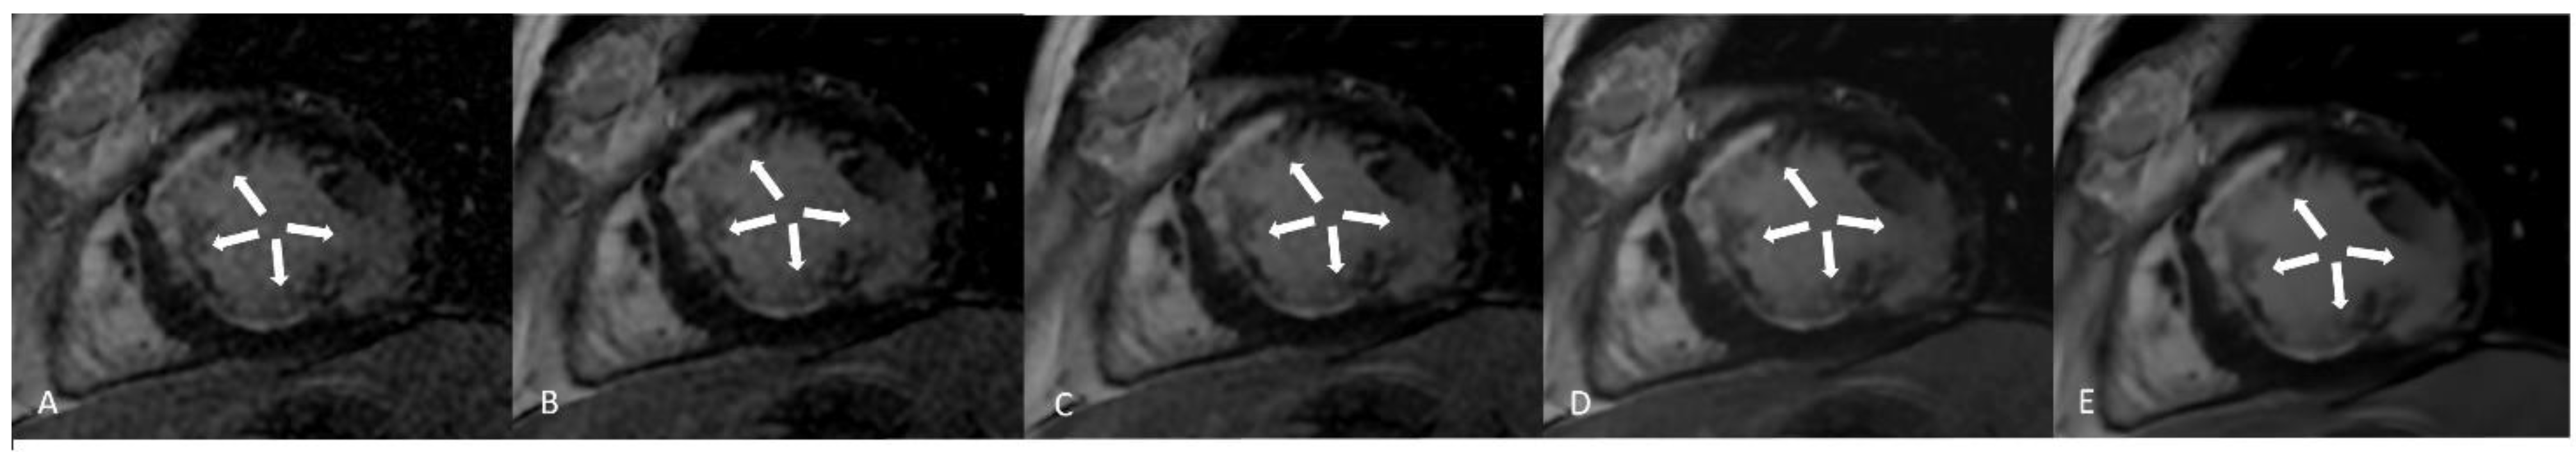

Improvement of image quality has been developed by several vendors by decreasing the noise of pictures (Figure 6). The “Deep Resolve” algorithm is a deep learning reconstruction able to decrease the noise of images. It is divided into “sharp” and “gain” reconstructions. In “Deep Resolve Gain” acquisition, the algorithm, starting from raw data, identifies the parts of images with more noise and increases the noise reduction in these parts [47]. In “Deep Resolve Sharp” acquisition the images enter the image reconstruction in a “high-resolution mode” while they are acquired with low resolution. The algorithm was trained on high-resolution images, so in the presence of low resolution pictures, the algorithm decreases the noise, simulating an image with high resolution from the raw data in order ensure the quality.

AIR Recon DL reconstruction is another technique that is able to increase signal-to-noise ratio, reduce truncation artifacts, and increase spatial resolution compared with standard reconstruction [42]. Using the AIR DL reconstruction, images can be reconstructed using “low”, “medium”, or “high” filters. The algorithm was created using millions of images, gradient backpropagation, and the ADAM optimizer. Compared with the previous algorithm, AIR DL has been evaluated in CMR [32]. Van der Velde et al. analyzed the impact of AIR DL on late gadolinium enhancement (LGE) images, demonstrating that it was possible to obtain LGE images with decreased noise [43]. Similar results were observed by Muscogiuri et al., who showed that it was possible to obtain images from multisegment LGE with the same image quality as those from standard single-segment LGE [32].